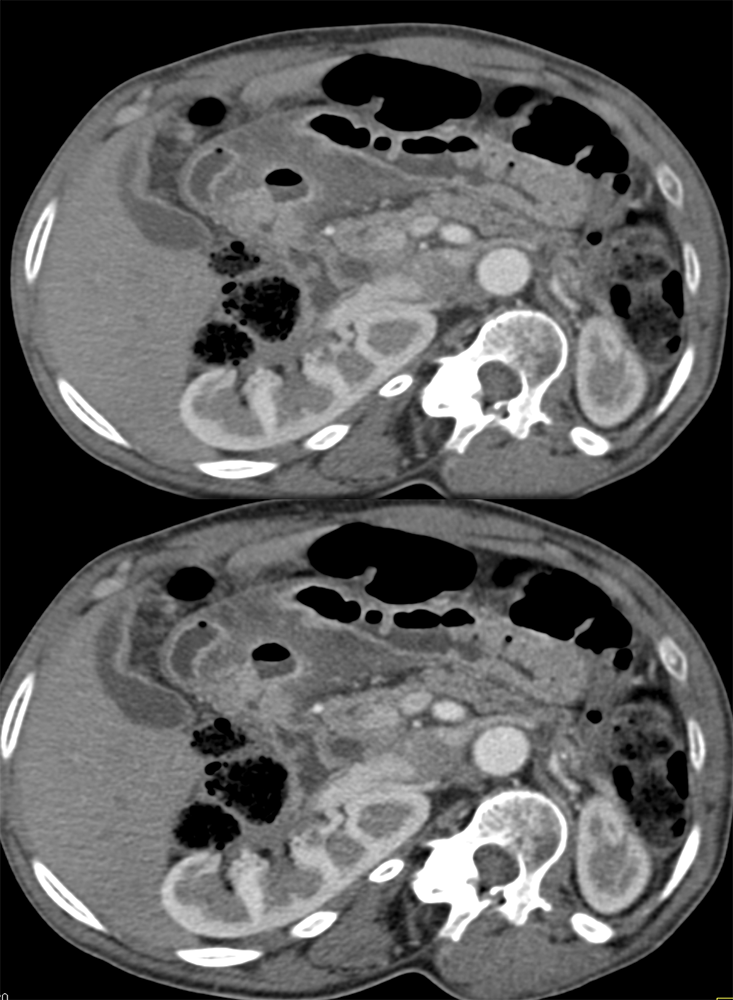

“Gastritis can be secondary to many etiologies including infection, systemic illness such as trauma or burns, and autoimmune disease. Peptic ulcer disease is most commonly caused by Helicobacter Pylori infection and chronic NSAID use . The most common sites for ulcer formation are the gastric antrum/pylorus and proximal duodenum. The resultant edema and fibrosis around the ulcer site can cause narrowing and eventual obstruction of the gastric outlet [9]. Prior to the widespread use of H2 blockers and proton pump inhibitors, peptic ulcer disease was the most common cause of gastric outlet obstruction, however in the era of H2 blockers, outlet obstruction now predicts malignancy. While endoscopy is the modality of choice for diagnosing gastritis, CT is often performed first particularly in the setting of acute abdominal pain.” Imaging of acute gastric emergencies: a case-based review Jetty S et al. Clinical Imaging 72 (2021) 97–113 |

“On imaging, it can be difficult to distinguish benign peptic ulcer disease from malignant causes of gastric outlet obstruction and biopsy is required for confirmation. Peptic ulcers can perforate and should be recognized on imaging.” Imaging of acute gastric emergencies: a case-based review Jetty S et al. Clinical Imaging 72 (2021) 97–113 |

“On CT, gastritis will appear as wall thickening with alternating hyper- and hypoattenuation representing mucosal enhancement and submucosal edema. The presence of mucosal enhancement (hyperemia) on CT suggests gastritis as the cause of gastric wall thickening. An uncommon form of gastritis is emphysematous gastritis. It is usually caused by gas-forming Escherichia coli. Initially obtained AXR may show mottled gas outlining the gastric wall. CT can confirm the diagnosis. Mottled gas can also be a sign of gastric pneumatosis from ischemia.” Imaging of acute gastric emergencies: a case-based review Jetty S et al. Clinical Imaging 72 (2021) 97–113 |

”Primary gastric cancer (GC) is a common cause of cancer related death worldwide and can initially present as a gastric ulcer. The characteristic CT finding in GC is disruption of the multilayered pattern of the gastric wall enhancement with thickening, variable enhancement and ulceration. Malignancy is the most common cause of gastric outlet obstruction. Malignant obstruction is an advanced disease presentation that occurs in up to 20% of patients with primary pancreatic, gastric, or duodenal carcinomas. It can be intrinsic or extrinsic. Extrinsic obstruction is almost always due to compression of the gastric outlet from tumor growth in surrounding organs. It is most commonly seen with primary tumors of the pancreas and duodenum.” Imaging of acute gastric emergencies: a case-based review Jetty S et al. Clinical Imaging 72 (2021) 97–113 |